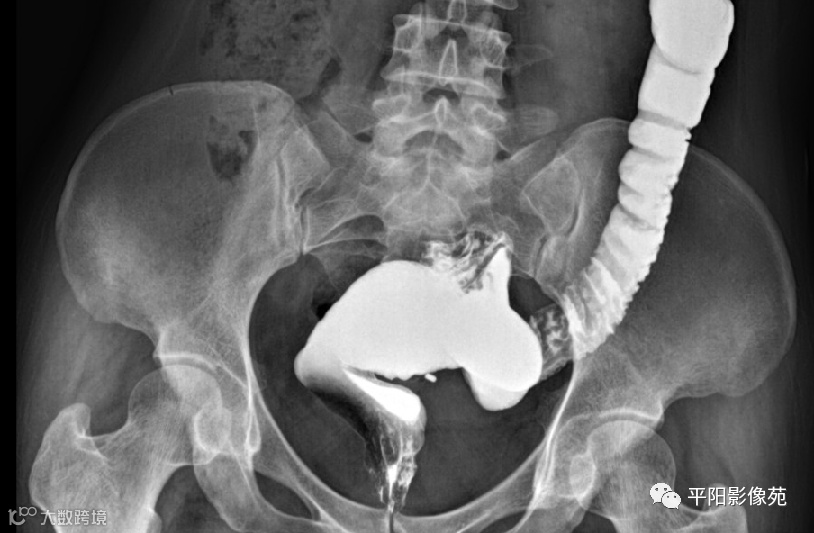

直肠脱垂

排粪造影

直肠壁部分或全层向下移位,称为直肠脱垂(rectal prolapse)

直肠壁部分下移,即直肠黏膜下移,称黏膜脱垂或不完全脱垂

直肠壁全层下移称完全脱垂

排便造影钡(x射线)排便造影或排便直肠造影是诊断排便障碍的公认临床

钡排粪造影实时评估直肠壁形态、盆底运动和排空。